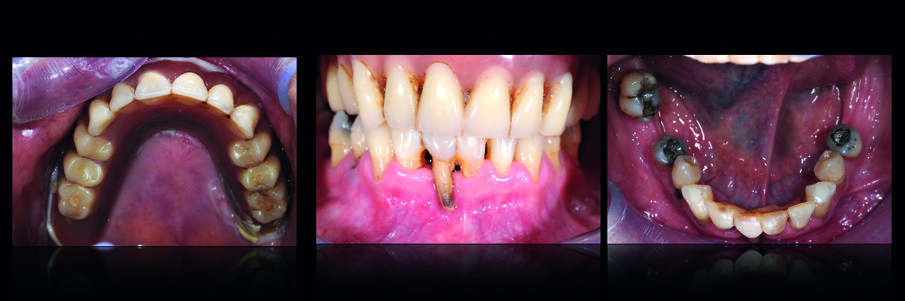

L’esame radiografico mostrava la persistenza di due impianti nel mascellare superiore (Fig. 1) uno dei quali pescava nella cavità nasale. Si osservava inoltre una lesione cistica in regione 4.1-4.2. Il trattamento dell’edentulia totale non può prescindere da una accurata analisi estetica che si concretizzerà in un’analisi Facciale, Dento-Labiale, Fonetica e Dentale. La paziente non mostrava esposizione dentale a riposo e presentava una linea del sorriso inversa (concava e non parallela al labbro inferiore) (Fig. 2). L’analisi del profilo della paziente confermava la necessità di fornire un adeguato supporto dei tessuti peri-orali nel mascellare superiore (Fig. 3). L’esame intra-orale permetteva di apprezzare l’insufficienza dell’estensione della protesi superiore, e la compromissione degli elementi dell’arcata inferiore. All’esame clinico i due impianti mostravano perdita dell’integrazione. (Figg. 4, 5).

Dopo la loro rimozione e aspettato il periodo di guarigione, sono state rilevate le impronte iniziali e, dopo aver costruito un porta-impronte ed il suo successivo bordaggio funzionale, è stata rilevata l’impronta di precisione del mascellare superiore. Sul modello master, è stato realizzato un vallo in cera che ha permesso la registrazione dei rapporti inter-mascellari e il montaggio dei modelli in articolatore tramite arco facciale. Sono state così realizzate una protesi rimovibile provvisoria superiore e una protesi fissa inferiore. In una seduta successiva sono stati estratti gli elementi inferiori non recuperabili e la protesi fissa inferiore è stata ribasata e stabilizzata sui pilastri residui (Fig. 6). Sono stati successivamente valutati i parametri funzionali ed estetici comparandoli con la situazione iniziale (Fig. 7), osservando il miglioramento della qualità del supporto dei tessuti periorali (Fig. 8). La fase successiva ha previsto la terapia implantare: previa adeguata ceratura è stata realizzata una guida chirurgica che ha permesso il posizionamento ideale degli impianti dentali nell’arcata inferiore (Fig. 9).